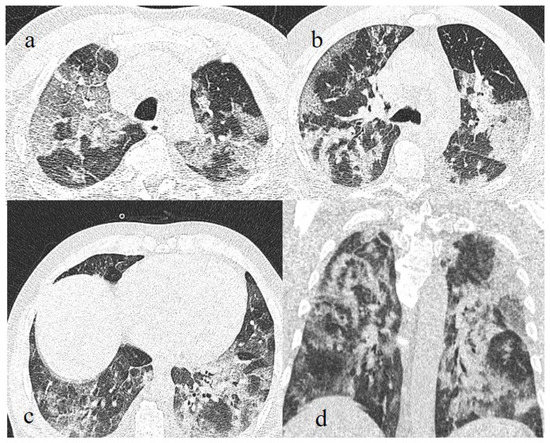

- Kanne, J.P.; Little, B.P.; Schulte, J.J.; Haramati, A.; Haramati, L.B. Long-term Lung Abnormalities Associated with COVID-19 Pneumonia. Radiology 2023, 306, e221806. [Google Scholar] [CrossRef]

- Han, X.; Fan, Y.; Alwalid, O.; Zhang, X.; Jia, X.; Zheng, Y.; Shi, H. Fibrotic Interstitial Lung Abnormalities at 1-year Follow-up CT after Severe COVID-19. Radiology 2021, 301, E438–E440. [Google Scholar] [CrossRef]

- Watanabe, A.; So, M.; Iwagami, M.; Fukunaga, K.; Takagi, H.; Kabata, H.; Kuno, T. One-year follow-up CT findings in COVID-19 patients: A systematic review and meta-analysis. Respirology 2022, 27, 605–616. [Google Scholar] [CrossRef]

- Bocchino, M.; Lieto, R.; Romano, F.; Sica, G.; Bocchini, G.; Muto, E.; Capitelli, L.; Sequino, D.; Valente, T.; Fiorentino, G.; et al. Chest CT–based Assessment of 1-year Outcomes after Moderate COVID-19 Pneumonia. Radiology 2022, 305, 479–485. [Google Scholar] [CrossRef] [PubMed]

- Cocconcelli, E.; Bernardinello, N.; Giraudo, C.; Castelli, G.; Giorgino, A.; Leoni, D.; Petrarulo, S.; Ferrari, A.; Saetta, M.; Cattelan, A.; et al. Characteristics and Prognostic Factors of Pulmonary Fibrosis After COVID-19 Pneumonia. Front. Med. 2022, 8, 823600. [Google Scholar] [CrossRef] [PubMed]